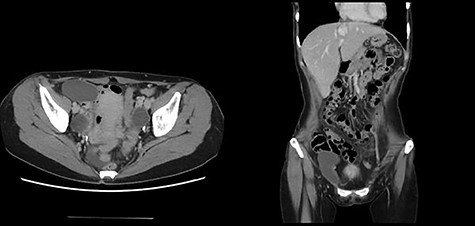

A 49-year-old woman presented with painless swelling in her right inguinal region. She had a history of caesarian section and no history of infantile inguinal hernia. Physical examination revealed a soft egg-shaped mass extending from the right inguinal region to the labia majora. The mass was seen as a protrusion when the patient was in the standing position, while it disappeared when the patient was in the lying position. Ultrasound revealed a well-defined hypo-echoic elongated mass that extended from the superficial inguinal canal, with no solid component (Fig. 1). Computed tomography (CT) showed that 55 × 34 × 95 mm oval fluid collection located at the right inguinal region near the cecum and retroperitoneum in the abdominal cavity (Fig. 2). Total colonoscopy found no mucosal abnormalities from the cecum to the rectum; however, a mass of tissue pushed the cecal wall from outside (Fig. 3). This hinted toward a large HCN, appendiceal tumor or retroperitoneal tumor; we decided to attempt a combined approach of conventional and laparoscopic methods for diagnosis and treatment of the swelling. We used three ports (12, 10 and 5 mm; Fig. 4) for our laparoscopic approach. We placed a 12 mm laparoscopic trocar into the umbilicus for CO2 insufflation of the pneumoperitoneum. Endoscopic intraperitoneal observation revealed that the mass was distant from the cecum and outside the peritoneum (Fig. 5). The tumor was large and was not completely observed using only an intra-abdominal approach. Therefore, we used a combined approach, which was the conventional method with a skin incision in the inguinal region in addition to the intra-abdominal method with laparoscopic approach. The tumor could be resected without any damage by observing from both directions (Fig. 6). We adopted the Direct Kugel Patch (ONFLEX®, C.R. Bard, Inc., USA) for the vulnerability of the posterior wall of the inguinal canal. Histopathological examination revealed that the mass contained single-layered mesothelial cells and no tumor or endometriosis. Based on imaging, histopathology and operative findings, we diagnosed her with an HCN. The patient recovered and did not have any postoperative complications, and she was discharged from hospital on postoperative day 6. She had no recurrence of hernia or hydrocele until 16 months postoperatively.